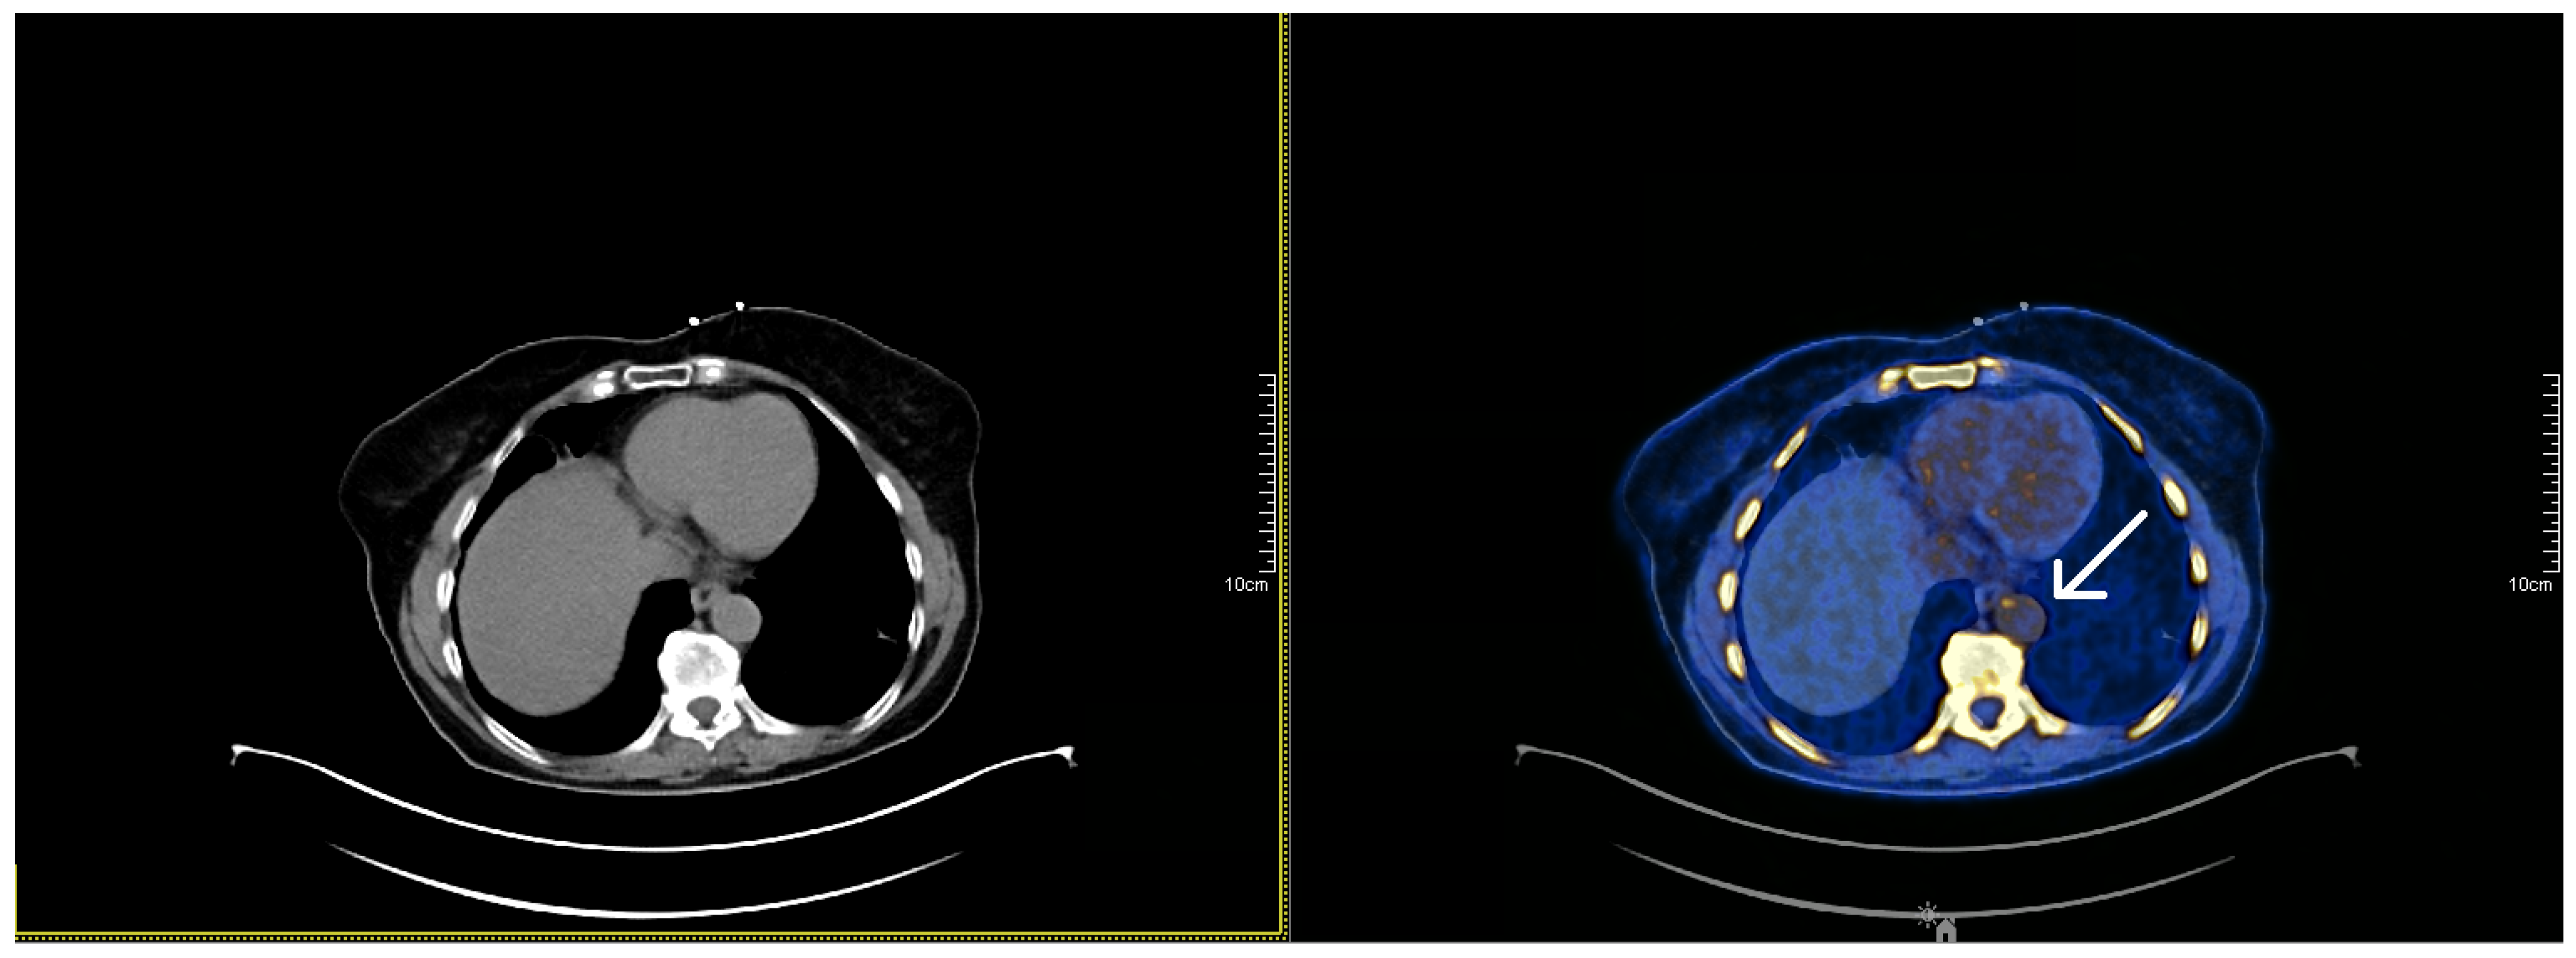

2.1. Imaging Inflammation with 18F-Fluorodeoxyglucose (FDG)